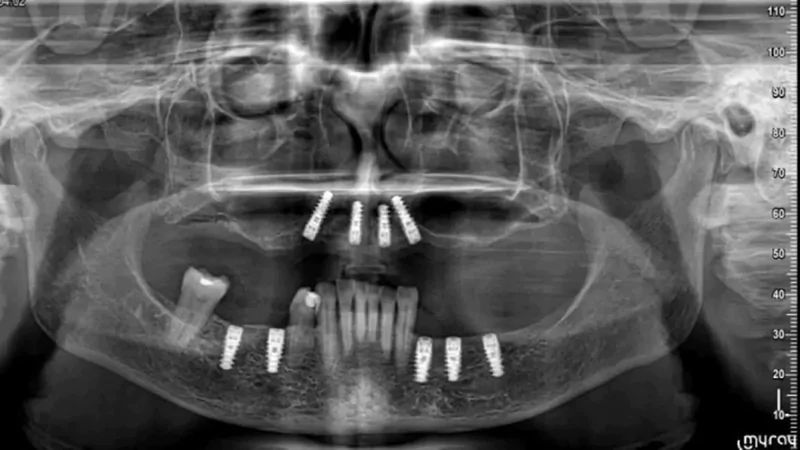

Since year 2000 we are Centre of excellence in implantology .We have done thousands of full mouth dental implant cases in last 25 years .We have a team approach where experienced implant surgeons , prosthodontists , maxillofacial surgeons , digital restorative dentists and lab technicians work together to deliver world class fixed teeth. We use multiple implant option from case to case. Some need All-on-4, some need All-on-6 or All-on-8 in selective cases.

All-on-4 Implants

It is a revolutionary concept in which only four implants support an entire arch of teeth. It is minimally invasive and cost-effective.

All-on-6 Implants

It is an advanced technique in which six implants support a full arch of teeth. It ensures superior stability, durability, and improved chewing function.